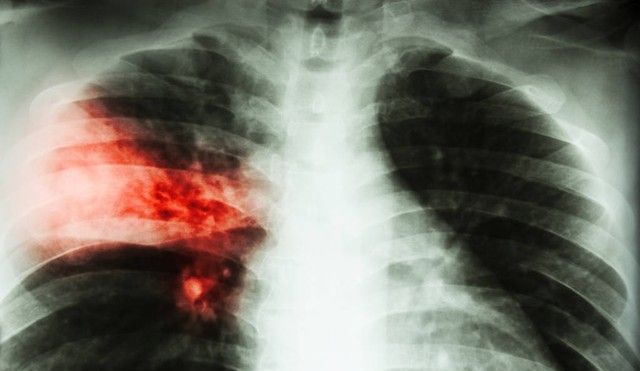

小李赶紧为她检查。患者名叫王芳,是一位小学老师。体温39.5度,咳嗽严重,胸片显示肺部感染。小李当机立断开具了左氧氟沙星。

以呼吸系统感染为例,左氧氟沙星对肺炎链球菌、流感嗜血杆菌等常见病原体均有良好抗菌活性。《中国成人社区获得性肺炎诊断和治疗指南(2016年版)》将其列为经验性治疗的首选药物之一。